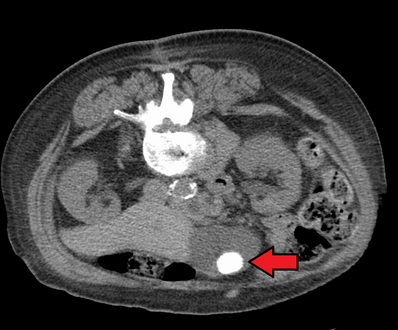

حصوة كبيرة في المرارة كما تظهر في الأشعة المقطعية.